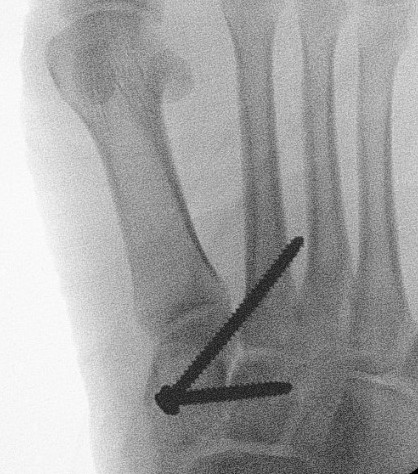

Screw fixation

AP view

- 1st metatarsal to medial cuneiform - screw

- 2nd metatarsal to intermediate cuneiform - screw

- medial cuneiform to base of second metatarsal - screw

+/- medial cuneiform to intermediate cuneiform - screw